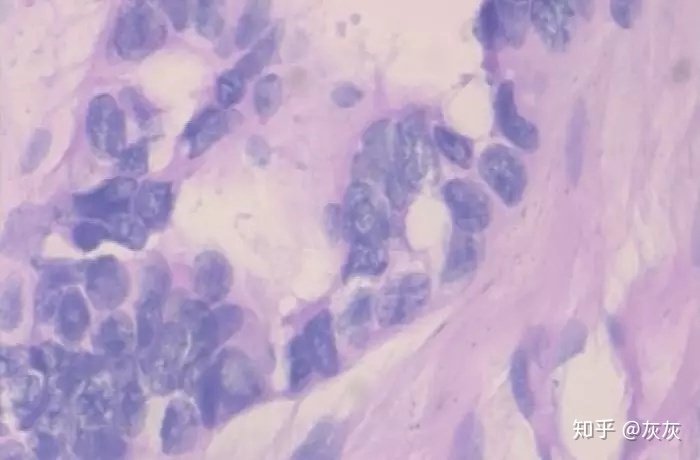

以上两张图片是良性样本

以上两张图片是恶性样本